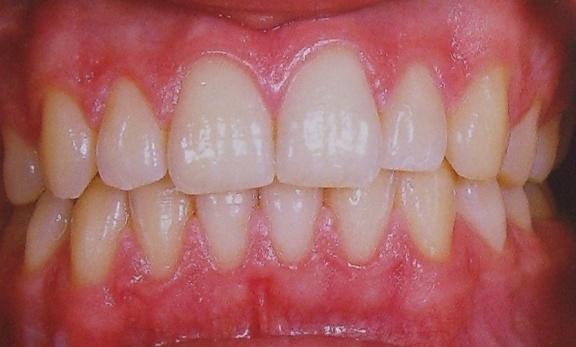

最终,小方接受了陈医生的治疗方案。经过牙周基础治疗后牙龈瘤体积缩小,陈医生通过牙周手术切除了困扰小方几个月的龈瘤。

准妈妈们可以自己对着镜子简单判断一下牙龈是否有炎症:健康的牙龈颜色呈淡粉色,菲薄而紧贴牙面。刷牙、吃东西都不会出血。

牙菌斑是妊娠期龈炎和妊娠期龈瘤发生的主要病因,治疗重点就是控制牙菌斑(牙周基础治疗)。经过完善的牙周基础治疗后,可获得理想的治疗效果,如剩下的妊娠瘤体积不大,可以在生完宝宝后进行手术治疗;而龈瘤体积较大,影响进食,可考虑在孕期进行手术切除。